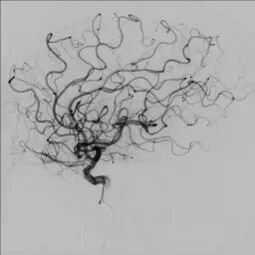

导丝怎么扩【载药时代 球扩天下】NOVA DES®颅内药物球扩支架在大脑中动脉重度狭窄中的应用——济南市第四人民医院使用体会一例!_https://www.jmylbn.com_新闻资讯_第5张

DWI

重要影像结论:左基底节区、放射冠区脑梗死,左大脑中动脉M1末端狭窄。

导丝怎么扩【载药时代 球扩天下】NOVA DES®颅内药物球扩支架在大脑中动脉重度狭窄中的应用——济南市第四人民医院使用体会一例!_https://www.jmylbn.com_新闻资讯_第6张

DSA

重要影像结论:左大脑中动脉M1末端重度狭窄。